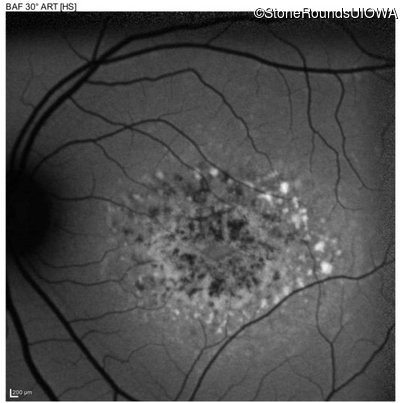

This 16 year old female first had difficulty seeing the blackboard at age 9. Her eye doctor at the time felt at the time that she was "faking it". More recently her eye doctor told her she would be blind by age 20 and suggested she get a seeing eye dog.

| AR Stargardt Disease | ABCA4 | Asp507Tyr GAT>TAT | IVS40+5 G>A | AR |